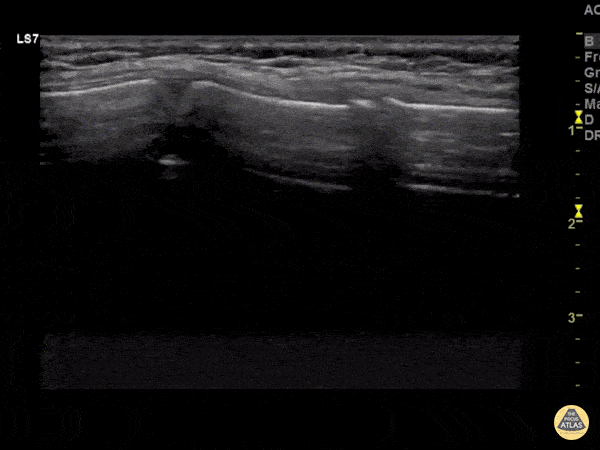

An 8 year old female presented with chest pain after a fall out of a bouncy house at her neighborhood block party. She has notable bony tenderness to the anterior chest wall over the sternum. POCUS revealed normal lung slide, but on evaluation of the sternum, a fracture was noted. In this clip the fracture is seen on the right as cortical disruption with surrounding trace hypoechoic hematoma formation. On the left side of the screen a normal growth plate is noted. Image courtesy of Dr. Paul Khalil Twitter: @khalil3paul